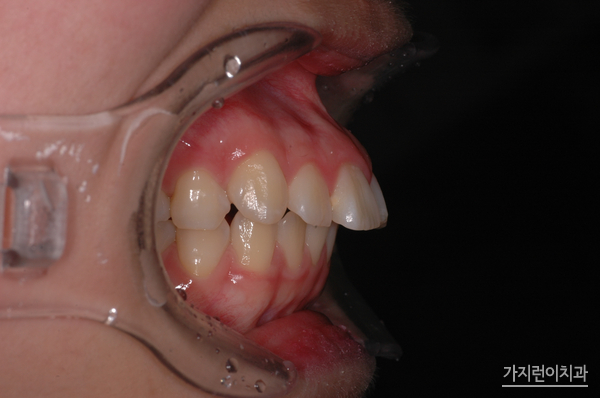

위 사진은 거미스마일과 돌출입 교정 전 측면 사진입니다. 이 케이스의 경우 약 1년 8개월 정도의 치료기간이 소요되었는데요. 치료가 끝난 후 7년이 지난 시점에도 개선된 상태를 안정적으로 유지해오는 걸 확인해볼 수 있었습니다.

환자 분의 거미스마일과 돌출입 증상은 위 사진과 같았습니다. 치아 돌출은 물론이고 잇몸이 과도하게 나타나는 증상 때문에 스트레스를 상당히 많이 받으셨는데요. 앞으로 나온 부분을 뒤로 집어넣기 위해 상하악 양쪽의 어금니를 발치하였고

미니스크류를 식립해 상악 전치의 후방과 함입 시키는 과정을 진행했습니다. 여기서 말하는 함입과정은 상악 전치를 위로 들어올리는 과정을 말하는데요. 충분한 힘을 주기 위해 미니스크류를 식립했으며

하악에도 미니스크류를 식립해 상하악 전치가 동시에 후방으로 들어갈 수 있도록 조치를 취했습니다. 이런 교정의 과정 끝에 1년 8개월이라는 시간이 소요 되었는데요. 하지만 수술적인 방법 없이 교정만으로도 돌출입교정과 거미스마일 치아교정을 성공적으로 마쳤기에 환자분의 만족도가 높았던 과정이었습니다.